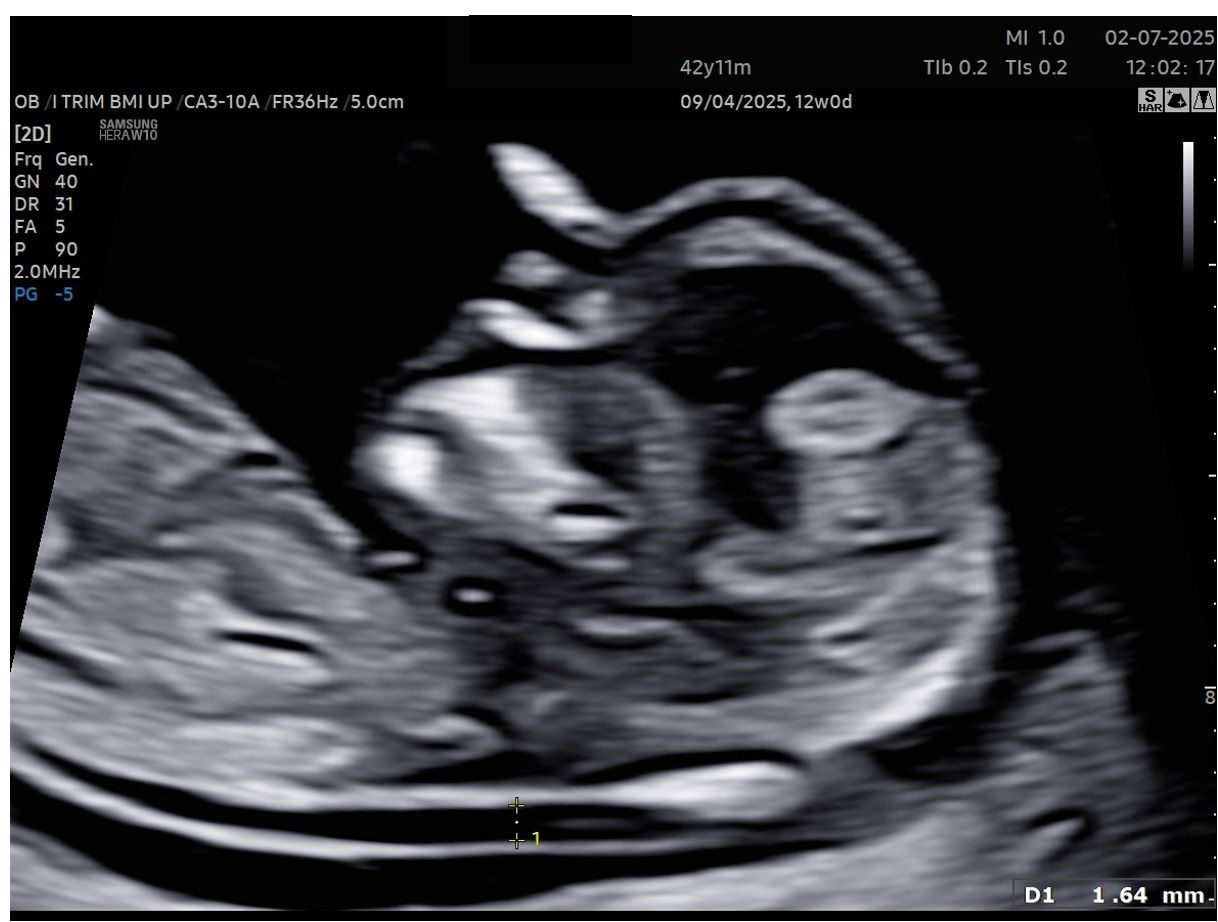

Laureata con Lode e Menzione alla carriera presso l’Università degli studi di Firenze e Specializzata con Lode presso L’ Università Cattolica del Sacro Cuore (Fondazione Policlinico A. Gemelli) mi occupo principalmente di Diagnostica Ecografica Ginecologica ed Ostetrica. Certificata dalla Fetal Medicine Foundation con sede a Londra per l’esecuzione dei Bitest, svolgo ecografie ostetriche per tutti i trimestri di gravidanza (premorfologiche, morfologiche, ecografia del III trimestre con flussimetria fetale).

Foto e video